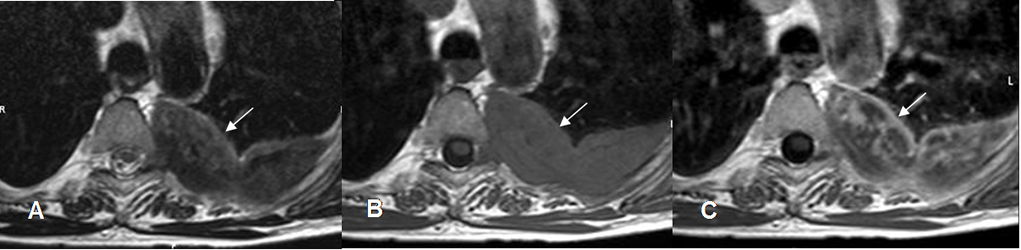

Fig 39 B. Mesotelioma.

A: RM axial en T2, B: RM axial en T1 simple y C: RM axial en T1 con contraste. Igual paciente anterior. Imagen de ubicación extrapleural, hipointensa en ambas secuencias por su contenido fibroso y que realza de forma heterogénea con el contraste, correspondiendo a mesotelioma.